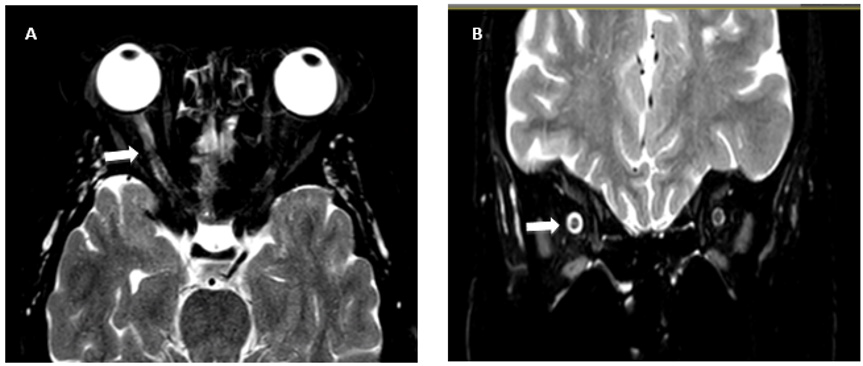

Brain MRI (Figure 1) showed a slight thickening and T2 hyperintensity of the right optic nerve sheath. The visual evoked response showed the presence of a demyelinating neuropathy in the right optic nerve (Figure 2). Optical coherence tomography showed an absence of intraocular axonal injury. Fortunately, three weeks after being discharged, the patient had progressively recovered her visual acuity as well as her colour vision without additional treatment. Brain MRI and visual evoked response performed later were normal.

Figure 1: T2-weighted brain MRI

(A) The axial section shows the proximal portion of the right optic nerve which appears swollen with high T2 signal (signalled

with a white arrow).

(B) The coronal section demonstrates that the thickening of the optic nerve is probably due to peripheral edema (signalled